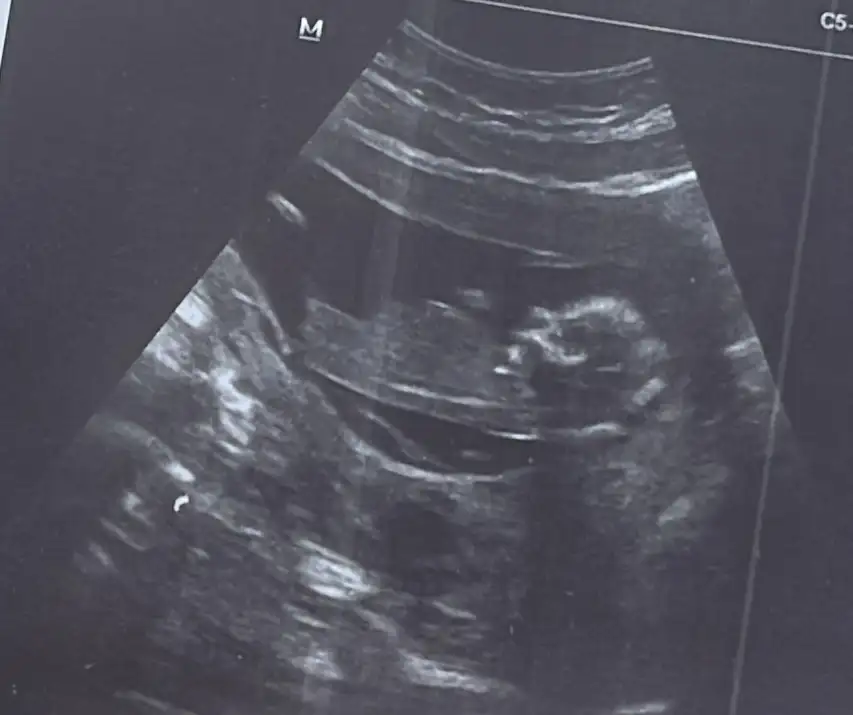

Maşallah bir kızımız daha geliyorkızlar 14. haftadan selamlar bugun fetal dna sonucum çıktı şükür temiz vee kızım oluyor![]()

Kızlarım merhaba benim dee 13+2 cinsiyet tahmininizi alabilir miyimMaşallah bir kızımız daha geliyorsağlıkla kucağınıza alın inşallah

Adı üstünde tahmin öncelikli sağlık olsun ama bence erkekKızlarım merhaba benim dee 13+2 cinsiyet tahmininizi alabilir miyim![]()

Doktor tahminimce kız gibi duruyor dedi ama nasıl anlaşılıyor anlamıyorum. Sen nerden erkek kanısına vardın canımAdı üstünde tahmin öncelikli sağlık olsun ama bence erkek![]()

Ben kendi ultrason görüntümle karşılaştırdım benim kızımın böyle bir görüntüsü yok ondan erkek gibi geldi öğrenirsen muhakkak yaz bana çok merak ettimDoktor tahminimce kız gibi duruyor dedi ama nasıl anlaşılıyor anlamıyorum. Sen nerden erkek kanısına vardın canım![]()

Bence kız gibi duruyor sosyal medyada görmüştüm ne kadar doğru bilmiyorum karnı yuvarlak bebişin kızların öyle oluyorKızlarım merhaba benim dee 13+2 cinsiyet tahmininizi alabilir miyim![]()